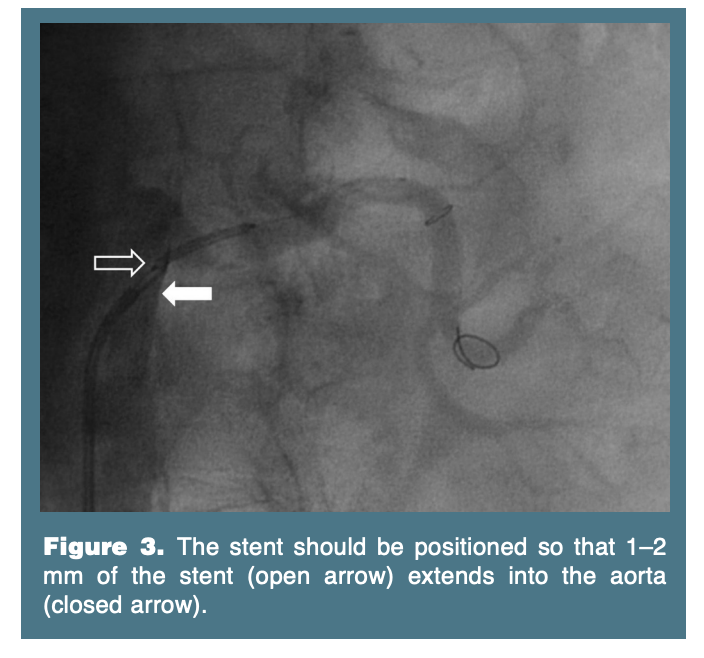

Balloon-expandable stents are typically utilized for renal arteries. Closed cell stent designs may be preferred, as they provide more radial strength at the renal ostium. Care should be taken so that 1–2 mm of the stent is within the aorta in order to assure that the ostium of the renal artery is covered (Figure 3). Orthogonal views should be employed to confirm proper stent placement. Improper placement of the stent with the ostium uncovered may contribute to restenosis or even stent embolization (Figure 4). It is our practice to retract the stent deployment balloon proximally and reinflate the balloon to a higher pressure, in an effort to flare the ostium of the stent in the aorta. Once this is achieved, the guide catheter can be advanced over the deflating balloon within the lumen of the stent for final angiography.